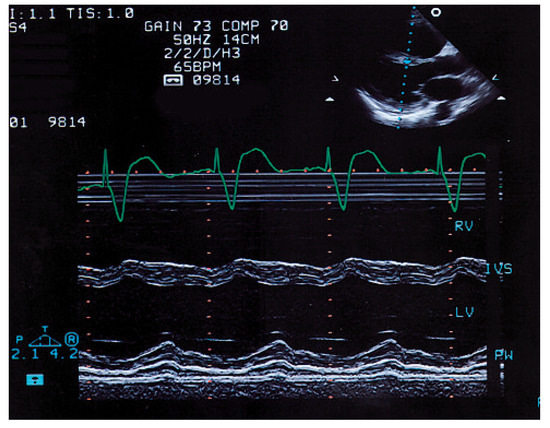

Summary. We report two cases of a 83- and a 78-year-old female with tetralogy of Fallot (TOF) who underwent operation at an advanced age in their 30’s, making them the oldest patients repaired for tetralogy of Fallot [...]